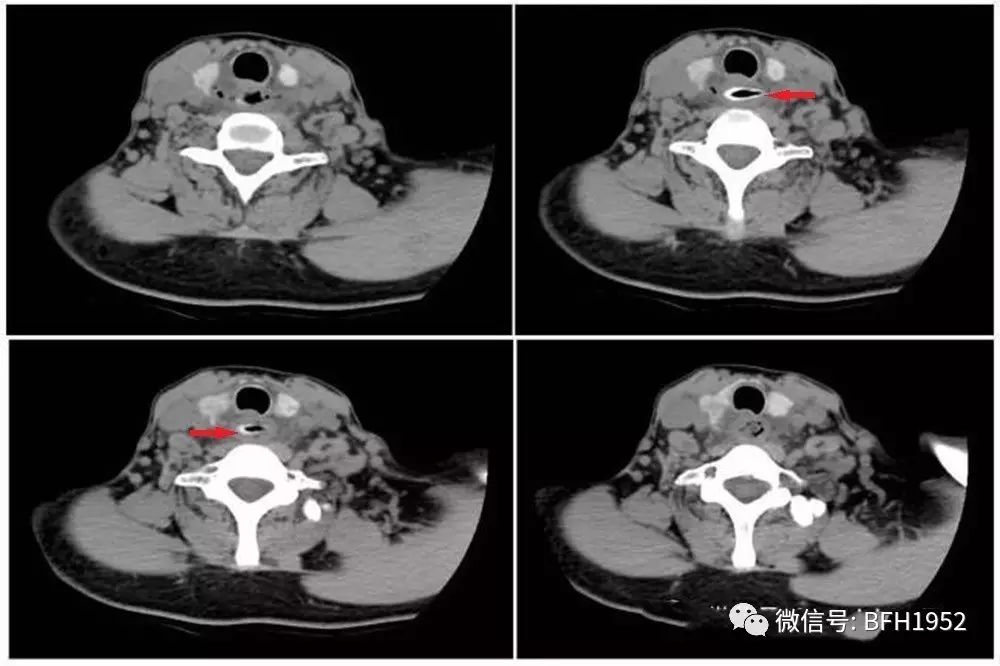

过了几天,患者吞咽困难的症状进一步加重并出现了右侧颈部疼痛。来到北京友谊医院后,医生通过颈部CT检查看见她的食道入口处有一枣核样异物,食管周围软组织少许肿胀伴有空气密度影,考虑是异物造成的食道穿孔伴有颈部间隙感染。经过急诊全麻硬食道镜终于将异物取出,目前患者恢复良好。

图1 第一例食道异物患者颈部CT平扫,轴位软组织窗可见食道入口处横行枣核样异物,食管周围组织少许肿胀,可见气体密度影